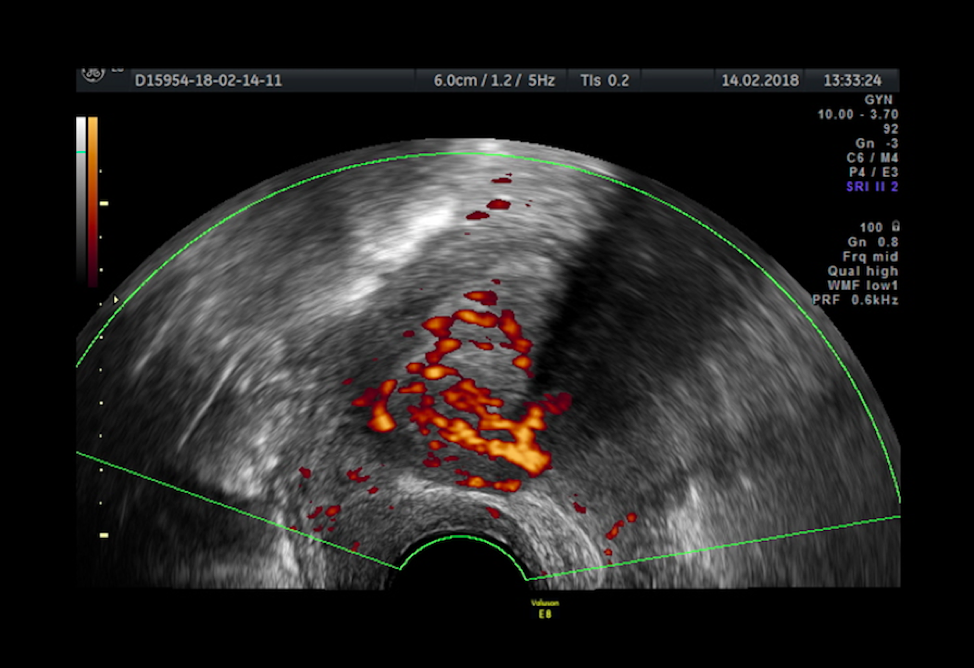

TVS has gained interest in recent years and is starting to be recommended as the first-line investigation technique in endometriosis because it allows extensive exploration of the pelvis, is widely available, cost efficient, and well tolerated [26,27,28].

TVS has the benefit of a lack of exposure to radiation and is the main method for the evaluation of adnexal masses, but remains limited for the diagnosis of other kinds of endometriosis.

Endometriomas have distinct characteristics on ultrasound: unilocular cysts, most often of homogenous “ground glass” appearance. The identification of an endometrioma should alert the clinician to the possibility of moderate-to-advanced stage disease. An important exception is postmenopausal women, in whom ovarian cysts with a “ground glass” appearance are associated with a 44% risk of malignancy. In addition, TVS may have a role in assessing disease involving the bladder and rectum [29].

TVS has the benefit of a lack of exposure to radiation and is the main method for the evaluation of adnexal masses, but remains limited for the diagnosis of other kinds of endometriosis. Endometriomas have distinct characteristics on ultrasound: unilocular cysts, most often of homogenous “ground glass” appearance. The identification of an endometrioma should alert the clinician to the possibility of moderate-to-advanced stage disease. An important exception is postmenopausal women, in whom ovarian cysts with a “ground glass” appearance are associated with a 44% risk of malignancy. In addition, TVS may have a role in assessing disease involving the bladder and rectum [29].